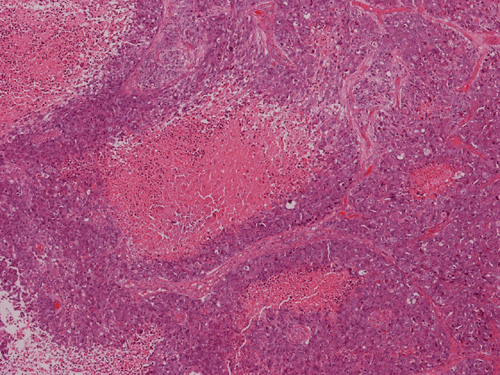

The volume of tissue received for examination amount to an aggregate of 4.0 x 2.0 x 1.5 cm in combined size. Grossly, the tissue is soft and has a creamy color with hemorrhage. The intraoperative cytologic preparation demonstrate a neoplasm composed with small to medium sized blue cells that smear out rather homgeneously and evenly. If you pay attention, there are some larger cells with a substantial amount of cytoplasm even at low magnification (Panel A). On high magnification, the nuclei are rather uniformly large, with high grade of pleomorphism, and almost all cells contain a distinct nucleoli. Apoptotic bodies and mitoses are frequent (Panel B). There are also large cells with prominent nucleoli and substantial amount of eosinophilic cytoplasm. These cells are suggestive of rhabdoid cells but none of them have the distinct inclusion body like cytoplasmic eosinophilic body of the rhabodid cells in atypical teratoid rhabodid tumor (Panel C). In the frozen section, both small to medium sized cells and cells with large nuclei with large, prominent, and eosinophilic nucleoli (Panel D and E). In the permanent sections, there is extensive necrosis (Panel F). The histology is in general agreement with that of frozen section except that the tumor cells appear to have more cytoplasm and more plemorphic, large nuclei with prominent nucleoli in comparison to the frozen section (Panel G). Large cells with substantial volume of cytoplasm, large, bizarre nucleoli and prominent, eosinophilic nucleoli are also noted (Panel H). There is a generalized degree of high grade pleomorphism. Results of immunohistochemistry are as follow:

Comment: This is an interesting case. Histologically, the overall morphology is consistent with a medulloblastoma with high grade of pleomorphism. Therefore, a diagnosis of large cell (anaplastic) medulloblastoma is the most likely diagnosis. The problem is the large cells with substantial amount of cytoplasm and large bizarre, eccentric nuclei with large nucleoli. These features raise the possibility of an atypical teratoid rhabdoid tumor (ATRT). These cells, if you observe carefully, lack the cytoplasmic, eosinophilic, inclusion body typical for rhabdoid cells. Nuclear wrapping is not readily seen. In fact, we did not find unmistakable nuclear wrapping until we looked at the immunohistochemistry for neurofilament. There are three immunohistochemical features in this case that are against a diagnosis of ATRT. First, vimentin is typically positive in most, if not all, tumor cells particularly those cells with rhabdoid changes. Second, most ATRT are positive for EMA. Third, the most powerful proof is the positive immunoreactivity of BAF47 which would be negative in ATRT. The negative result for desmin is helpful in ruling out the possibility of a rhabdomyosarcoma.

Large cell and anaplastic medulloblastomas are recognized as different variants in the new WHO classficiation 1. They share many basic features with medulloblastoma 2, 3. The most notable differences are large cell size, increased variation of nuclear size, prominent and even eosinophilic nucleoli, increased mitotic figures and number of pyknotic or apoptotic cells, and extensive, geographic areas of necrosis. In the experience of the authors, most of the tumor cells in large cell and anaplastic medulloblastomas have high nuclear to cytoplasmic ratio in a manner similar to that of the classic variant. As per the new WHO classification, large cell medulloblastomas are composed mainly of large cells with more cytoplasm than the classic variant or the anaplastic variant. In the experience of the authors, this distinction is not always possible. The case being illustrated here includes some large cells with substantial amount of cytoplasm and but these cells only represent a portion of the tumor cell population. In general, anaplastic and large cell medulloblastomas have less favorable prognosis than the classic variant of medulloblastoma. However anaplastic changes are uncommon and does not affect the prognosis in adult cases as per one study 4.

Immunohistochemistry, both classic, anaplastic, and large cell variants are similar. Immunoreactivity for synaptophysin can be demonstrated in most of the tumors. A small tumor that is negative for synaptophysin should raise a serious questions about the diagnosis of medulloblastoma. Expression of other markers such as neurofilament proteins, markers of photoreceptors, and glial fibrillary acidic protein (GFAP) can be seen. In contrast to glial tumors, mutation of p53 is quite uncommon. Isochromosome 17 is the most consistent genetic changes but it should not be used as a diagnostic tool. C-MYC gene amplification is also a common genetic alteration and has been shown to be related to anaplasia . Although studies have linked c-myc and N-myc gene overexpression with anaplasia and a poorer prognosis, this still appears somewhat controversial 5, 6, 7. Based on a study with gene expression profile 8, medulloblastoma with better prognosis are associated with expression of genes that influence cerebellar differentiation (incluing the TRKC and sodium channel gene) and extracellular matrix genes (including elastin and collagen type V gene). Expression of cell proliferation and gene metabolism (including MYBL2 and LDH) are associated with bad prognosis. Epithelial membrane antigen (EMA) is usually negative in medulloblastoma. The possibility of an atypical teratoid rhabdoid tumor (ATRT) should be considered when a medulloblastoma-like tumor with positive immunoreactivity for EMA must be considered. Expression of cytokeratin can be present in a spotty manner. Extensive expression of cytokeratin should raise the possibility of a metastatic carcinoma.